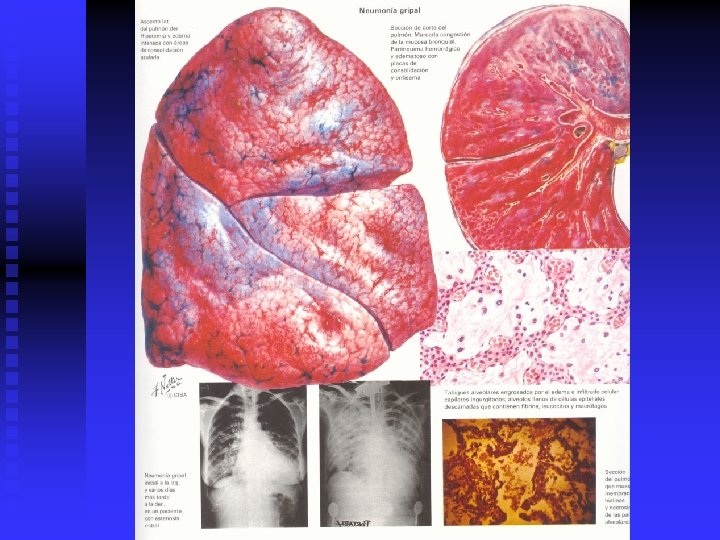

CUADRO CLINICO I n n Síndrome de Neumonía Típica: Inicio brusco, escalofrío, fiebre alta, tos productiva, dolor torácico. Estado tóxico, estertores crepitantes. Rx. Infiltrados alveolares. Etiología. Bacterias: neumococo, haemofilus influenciae, S. Aureus, K. Neumoniae.

CUADRO CLINICO II n n n Síndrome de Neumonía atípica: Inicio insidioso, fiebre irregular, tos seca, artralgias y mialgias, cefalea, diarrea y vómitos. EF: estertores variables, taquipnea, hipotensión y taquicardia. Rx. Infiltrados intersticiales Etiología: Mycoplasma, Clamydia, Legionella, virus

Clasificación Radiológica n Neumonía lobar, acinar o de los espacios aéreos n Neumonía de focos múltiples. Bronconeumonía n Neumonía intersticial n Neumonía necrotizante o cavitaria